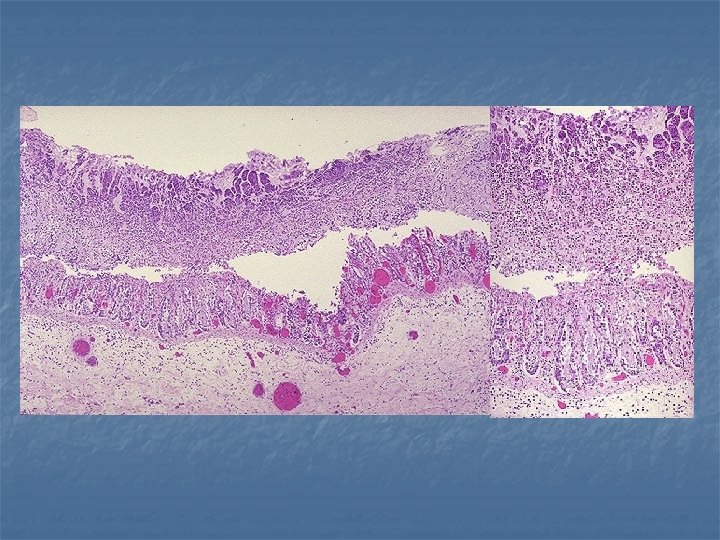

n Fully developed severe, active inflammation: n n n extensive and broadbased ulceration of the mucosa in the distal colon or throughout its length Isolated islands of regenerating mucosa bulge upward to create “pseudopolyps. ” Often the undermined edges of adjacent ulcers interconnect to create tunnels covered by tenuous mucosal bridges. n n The ulcers are frequently aligned along the axis of the colon (as with CD) In contrast to Crohn’s disease: n n rarely do the linear serpentine ulcers mural thickening does not occur Progressive mucosal atrophy in chronic cases Microscopy: n n n diffuse mononuclear inflammatory infiltrate in the lamina propria, admixed with neutrophils occasional eosinophils and mast cells.

Diffuse mononuclear cell infitration Pseudopolyps (carpet-like mucosa) pseudopolyp ulcer

Crypt abscess